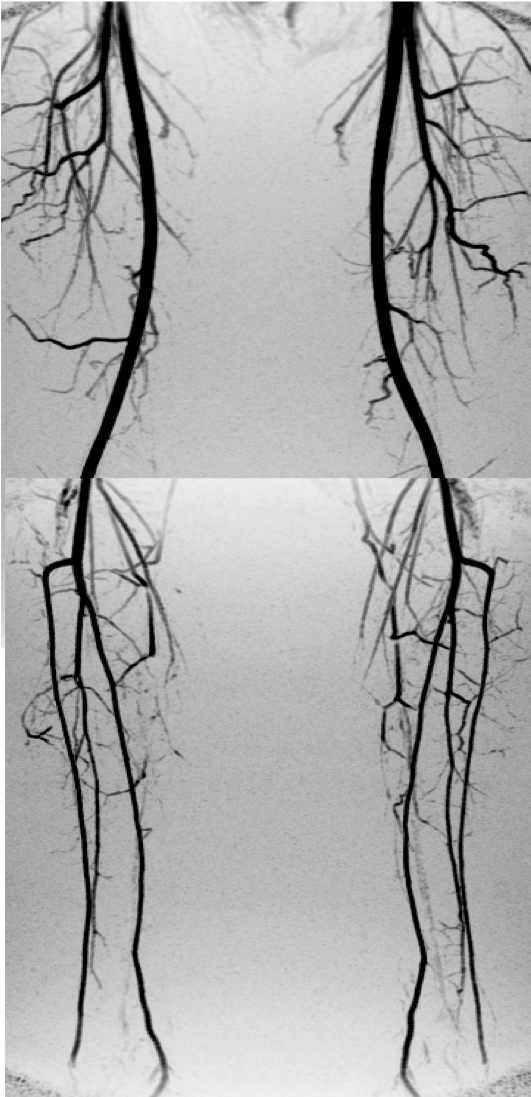

Since then, Frank Korosec has refined the vascular imaging methods into an approach called Time Resolved Imaging of Contrast Kinetics, or TRICKS. This technique takes 3D images over a set period after the patient is injected with a contrast agent. The contrast agent takes time to move through the patient’s circulatory system, and the time varies based on the patient's age and heath. But TRICKS takes the guesswork out of timing so the clinician can identify the vessel with the strongest MR signal. Clinicians can monitor the actual flow through the vessels to identify a possible blockage.

width= Top image: An MR image of the upper body using an approach called Time Resolved Imaging of Contrast Kinetics, or TRICKS, and GE’s new Air Coil technology, a lightweight blanket-like coil that conforms to the patient’s body to deliver improved images. Above: A TRICKS image of the vascular system. Images credit: GE Healthcare/University of Wisconsin-Madison.